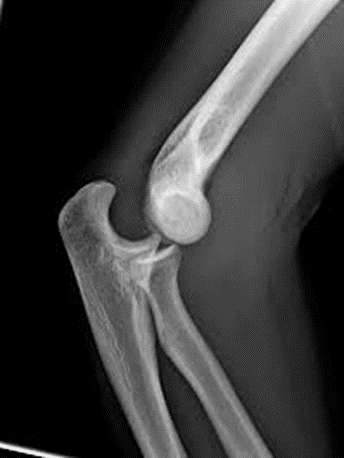

Fractura supracondílea del húmero

(frecuente en niños).

En estas fracturas se afecta la parte distal del húmero.

Suelen producirse por caídas sobre la mano o sobre el codo. Los pacientes experimentan un dolor agudo intenso e impotencia funcional (incapacidad para mover el codo).

Las fracturas de capitellum son fracturas que afectan a una pequeña parte del húmero distal. Las fracturas supracondíleas o supraintercondíleas son lesiones en las que se fractura de una forma más extensa el húmero distal.

Debido a la afectación articular, son fracturas que habitualmente requieren tratamiento quirúrgico mediante la colocación de tornillos, placas, e incluso en pacientes seleccionados, prótesis de codo.